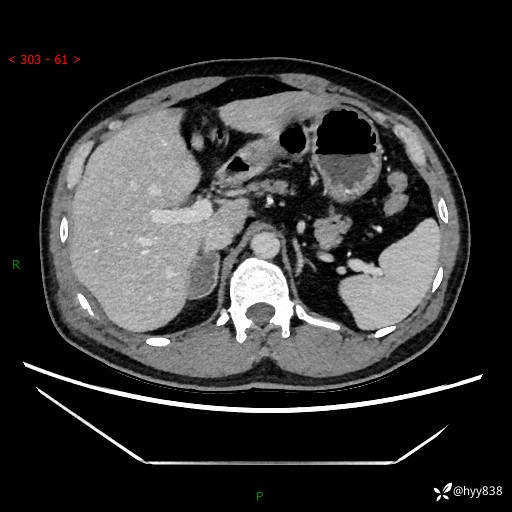

现病史:患者9月4日摔伤在深圳市宝安区中心医院行CT检查提示右侧肾上腺区结节(38*27mm),复查B超提示右侧肾上腺区可见一61*24mm异常低回声团,建议进一步检查。进一步完善增强CT后提示:右侧肾上腺区肿块及周围渗出改变,大致同前,考虑肾上腺腺瘤,不除外瘤内出血可能,否认阵发性头晕、头痛、出汗、乏力等不适,门诊以“ 右侧肾上腺肿瘤”收入住院。 起病来,患者精神、食欲、睡眠可,大便通畅,小便如上述,体力体重无明显改变。

肾上腺CT平扫

增强(动脉期+静脉期)

单侧肾上腺病变,鉴别诊断有哪些